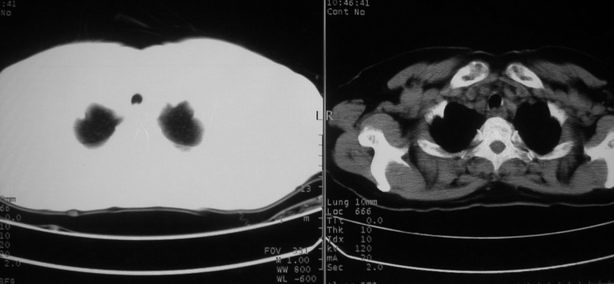

以下是引用zhangzhongshou在2008-5-22 12:51:00的发言:[br]左肺上叶肺癌并左侧胸腔积液可能性大。

以下是引用w_jianhua在2008-5-22 12:59:00的发言:[br]1.左肺上叶肺癌并左侧胸腔积液可能性大。2不除外支气管内膜结核并包裹性胸腔积液,建议支气管镜检3.左肺下叶肺大泡,肺气肿